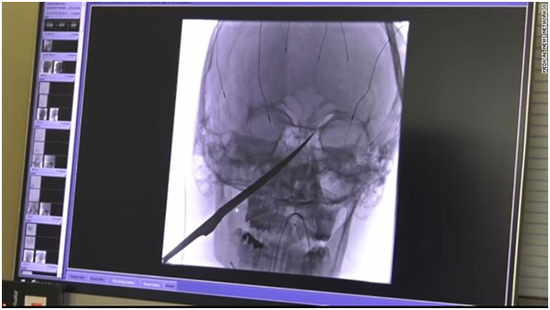

(格雷格头部的x光扫描图像.图源:cnn)